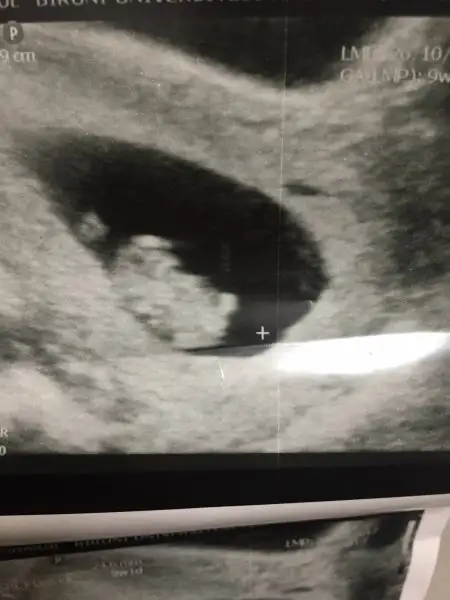

Teyzoslari bakin benim minik kurabiyem kocaman oldu bugun kontrolumuz vardi icimde kipir kipir hareket ediyordu cok duygulandim elimde olsa Sabah a kadar izlerdim onu ilk Hamilelik olunca acaip oluyorum farkli hissediyorum :emir_bebek::anneadayı:

Ooyy kıpırdıyor muydu canimm nasill yanii:KK64:9.haftada kipirdiyor mu minislerimiz